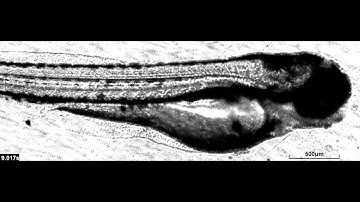

Zebrafish blood flow evaluation using a microscope- MicroZebraLab